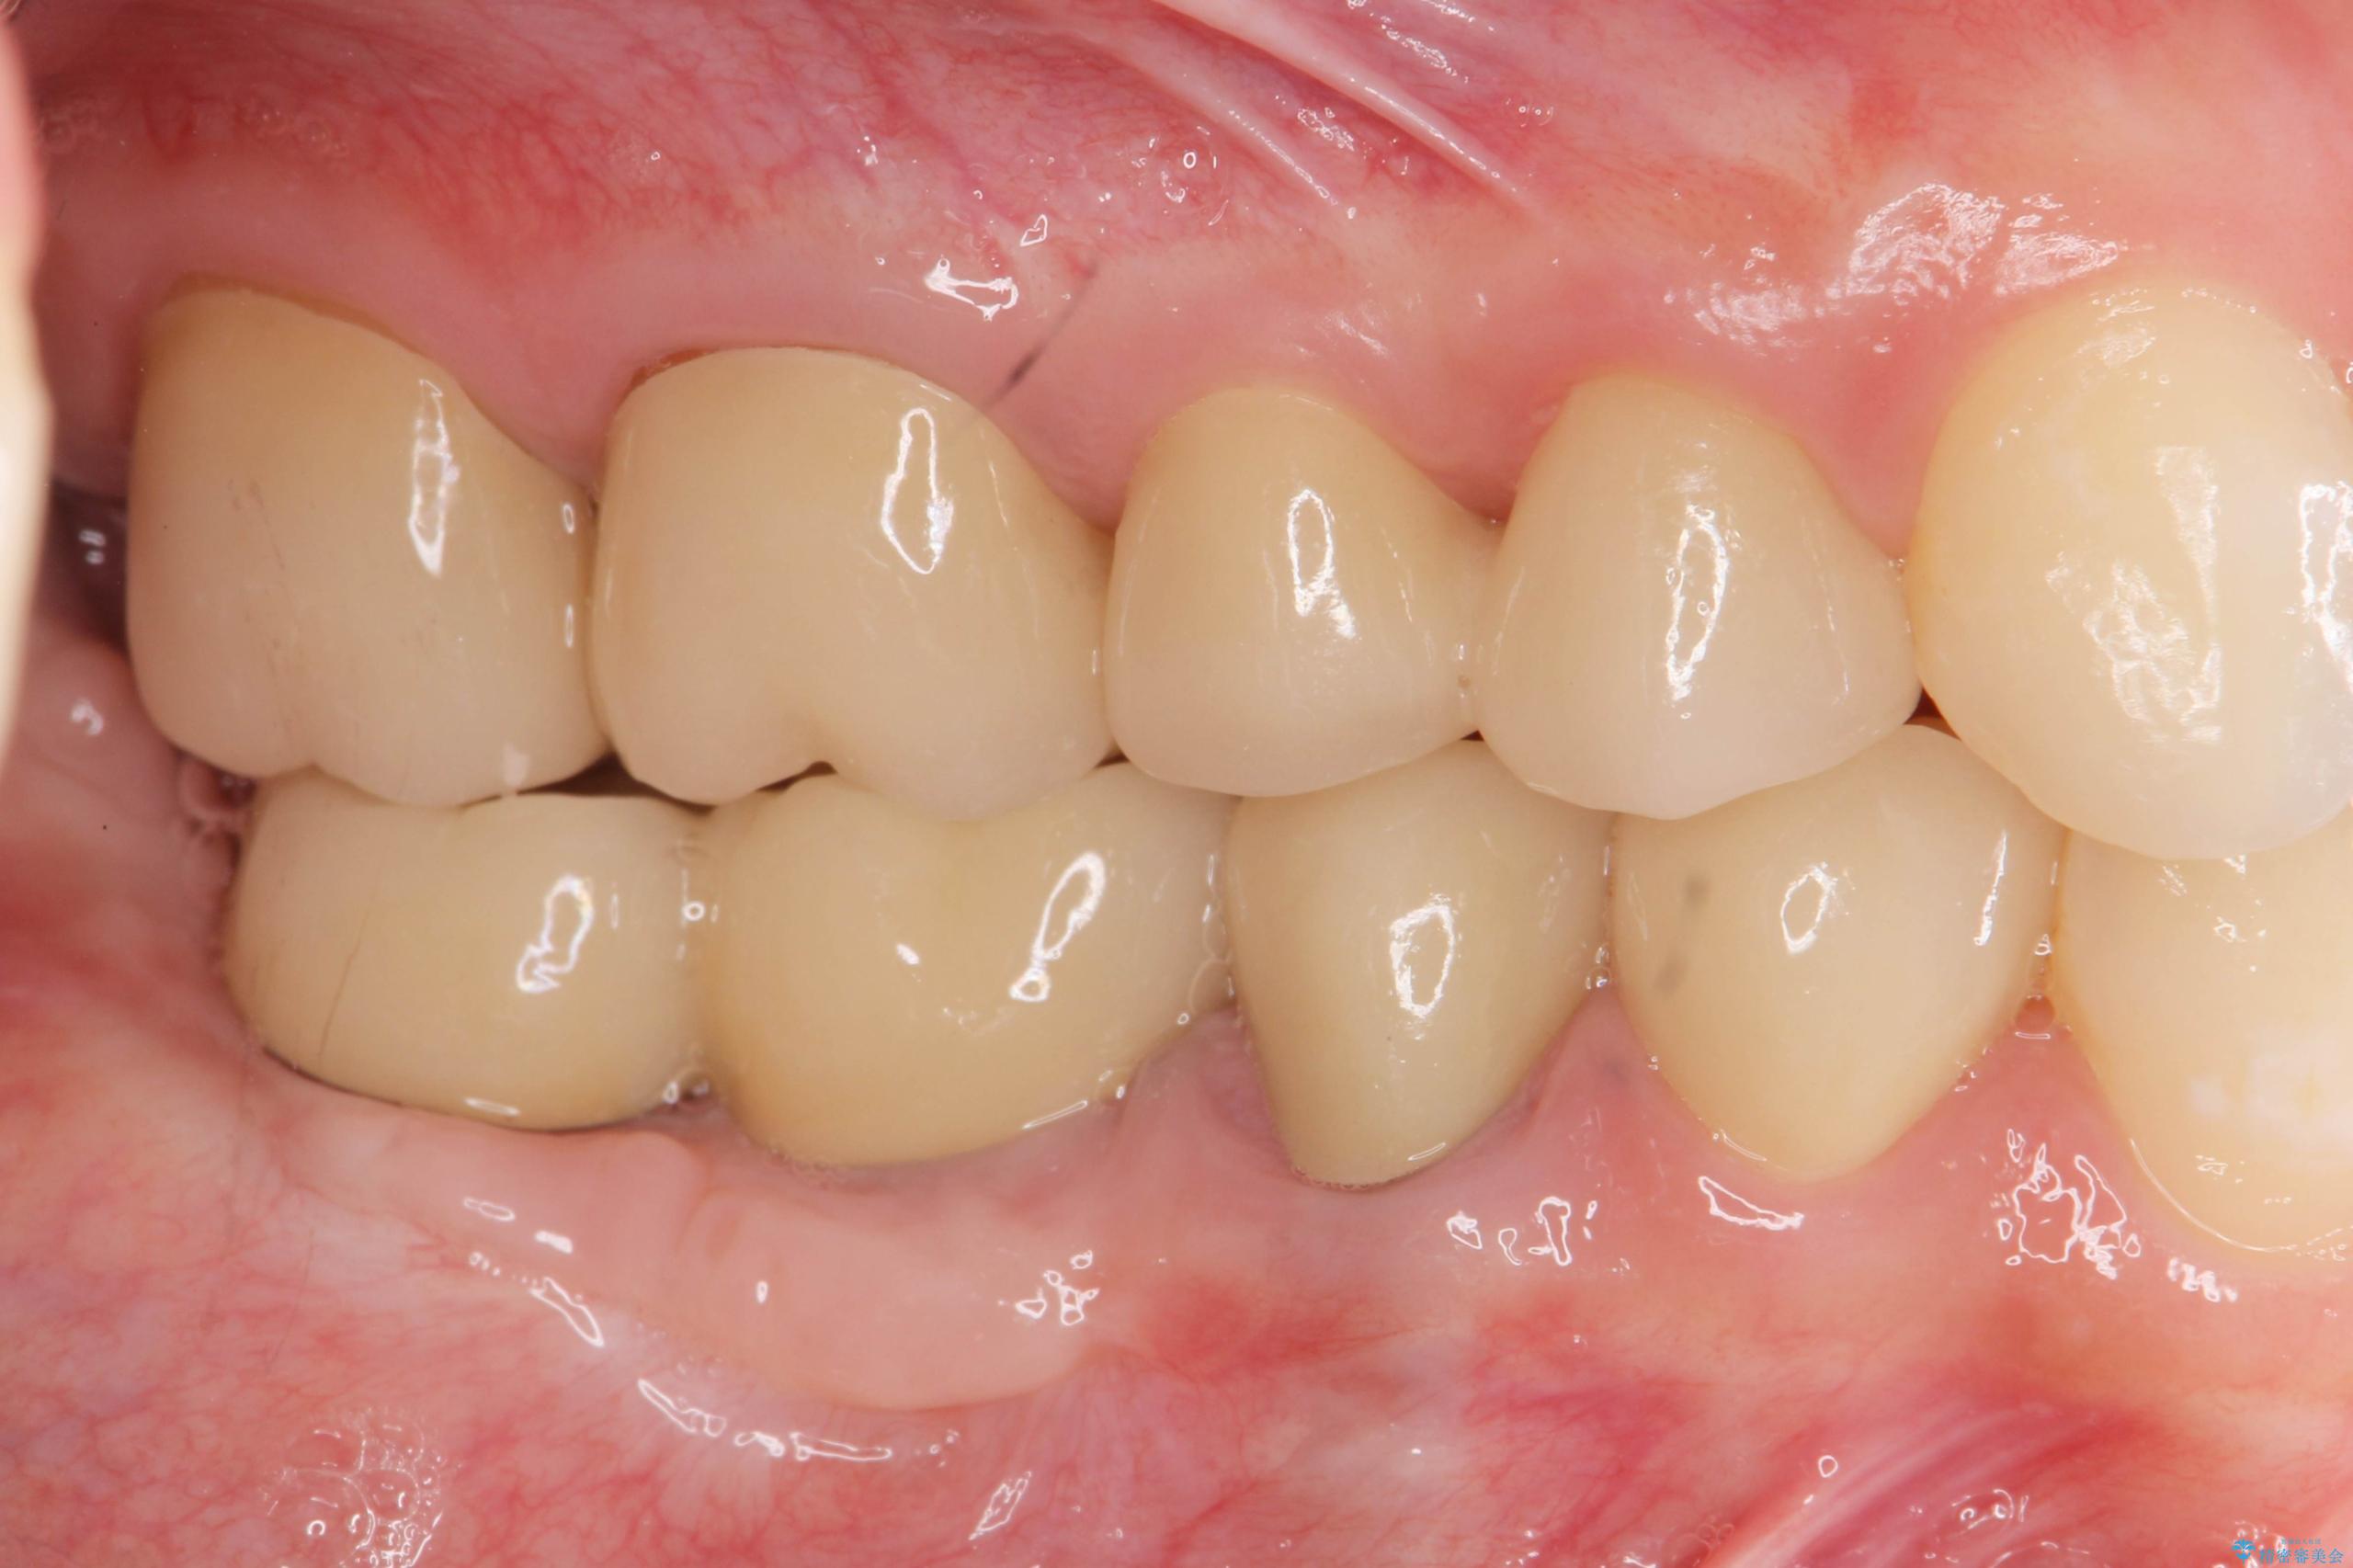

治療後

遊離歯肉移植術を伴うインプラント治療 治療後画像 遊離歯肉移植術を伴うインプラント治療 治療後画像 遊離歯肉移植術を伴うインプラント治療 治療後画像 遊離歯肉移植術を伴うインプラント治療 治療後画像